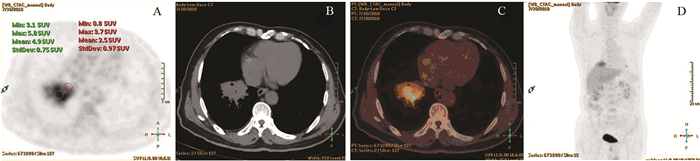

肺癌组P/D>1者占91.5%(65/71),炎性病变组P/D<1者占80.6%(25/31),两组差异有统计学意义(P<0.001)。以P/D>1为标准,对肺癌诊断的敏感度为91.5%,特异性为80.6%,准确性88.2%,见表 1,图 2~3。

图 2 一例典型的肺癌PET/CT图像Figure 2 PET/CT image of one typical case of lung cancerPatient, male, 67 years old. A moderately differentiated adenocarcinoma on the upper lobe of the right lung, the size was about 5.3×6.2cm, SUVmax was 11.1. Image A, B, C and D showed PET axial tomography image, CT axial tomography image, PET/CT fusion image and body maximum intensity projection (MIP). The PET images showed that the SUVmax of proximal part was 10.2, the SUVmax of distal part was 5.9, P/D value was 1.73![]() 图 3 肺炎性病变的PET/CT图像Figure 3 PET/CT image of inflammatory lung lesionPatient, male, 37 years old. An inflammatory infiltration with lung abscess on the lower lobe of the right lung, the size was about 5.9×4.3cm, SUVmax was 5.9. Image A, B, C and D showed PET axial tomography image, CT axial tomography image, PET/CT fusion image and body MIP. The PET images showed the SUVmax of proximal part was 3.7, the SUVmax of distal part was 5.8, P/D value was 0.64

图 3 肺炎性病变的PET/CT图像Figure 3 PET/CT image of inflammatory lung lesionPatient, male, 37 years old. An inflammatory infiltration with lung abscess on the lower lobe of the right lung, the size was about 5.9×4.3cm, SUVmax was 5.9. Image A, B, C and D showed PET axial tomography image, CT axial tomography image, PET/CT fusion image and body MIP. The PET images showed the SUVmax of proximal part was 3.7, the SUVmax of distal part was 5.8, P/D value was 0.643 讨论